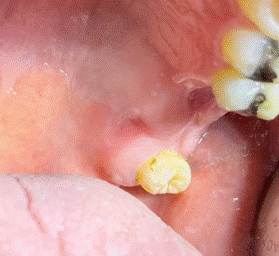

Al examen clínico intraoral, se pesquizan dientes 2.6 y 2.7 en estado radicular y aumento de volumen palatino. (Figura 1) Destaca presencia de úlcera de aspecto crateriforme, fondo sucio y bordes definidos de 10 x 10 mm de diámetro. Se realiza exodoncia de restos radiculares y se indica colutorio de clorhexidina al 0,12% 2 veces al día por 7 días para mejorar las condiciones locales y disminuir el componente inflamatorio. Se cita a control en 1 semana para valorar necesidad de biopsia y estudio histopatológico.

En el control refiere menor sintomatología y al examen se observó una franca regresión de la ulcera (Figura 2), presencia de fibrina en el fondo y disminución de signos inflamatorios. Se decidió no realizar biopsia, por hipótesis diagnóstica de sialometaplasia necrotizante. Los controles continuaron durante las 4 semanas siguientes observándose al cabo de un mes una completa reparación del tejido (Figura 3).